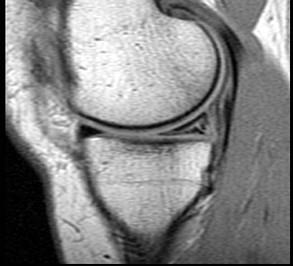

问题 男,29岁,左膝关节有外伤史,膝关节疼痛,活动受限,请结合所提供的图像,选择最佳选项 ( )

选项 A、内侧半月板内侧撕裂 B、后十字韧带撕裂 C、前十字韧带撕裂 D、内侧半月板外周后角垂直撕裂 E、未见异常

答案 A